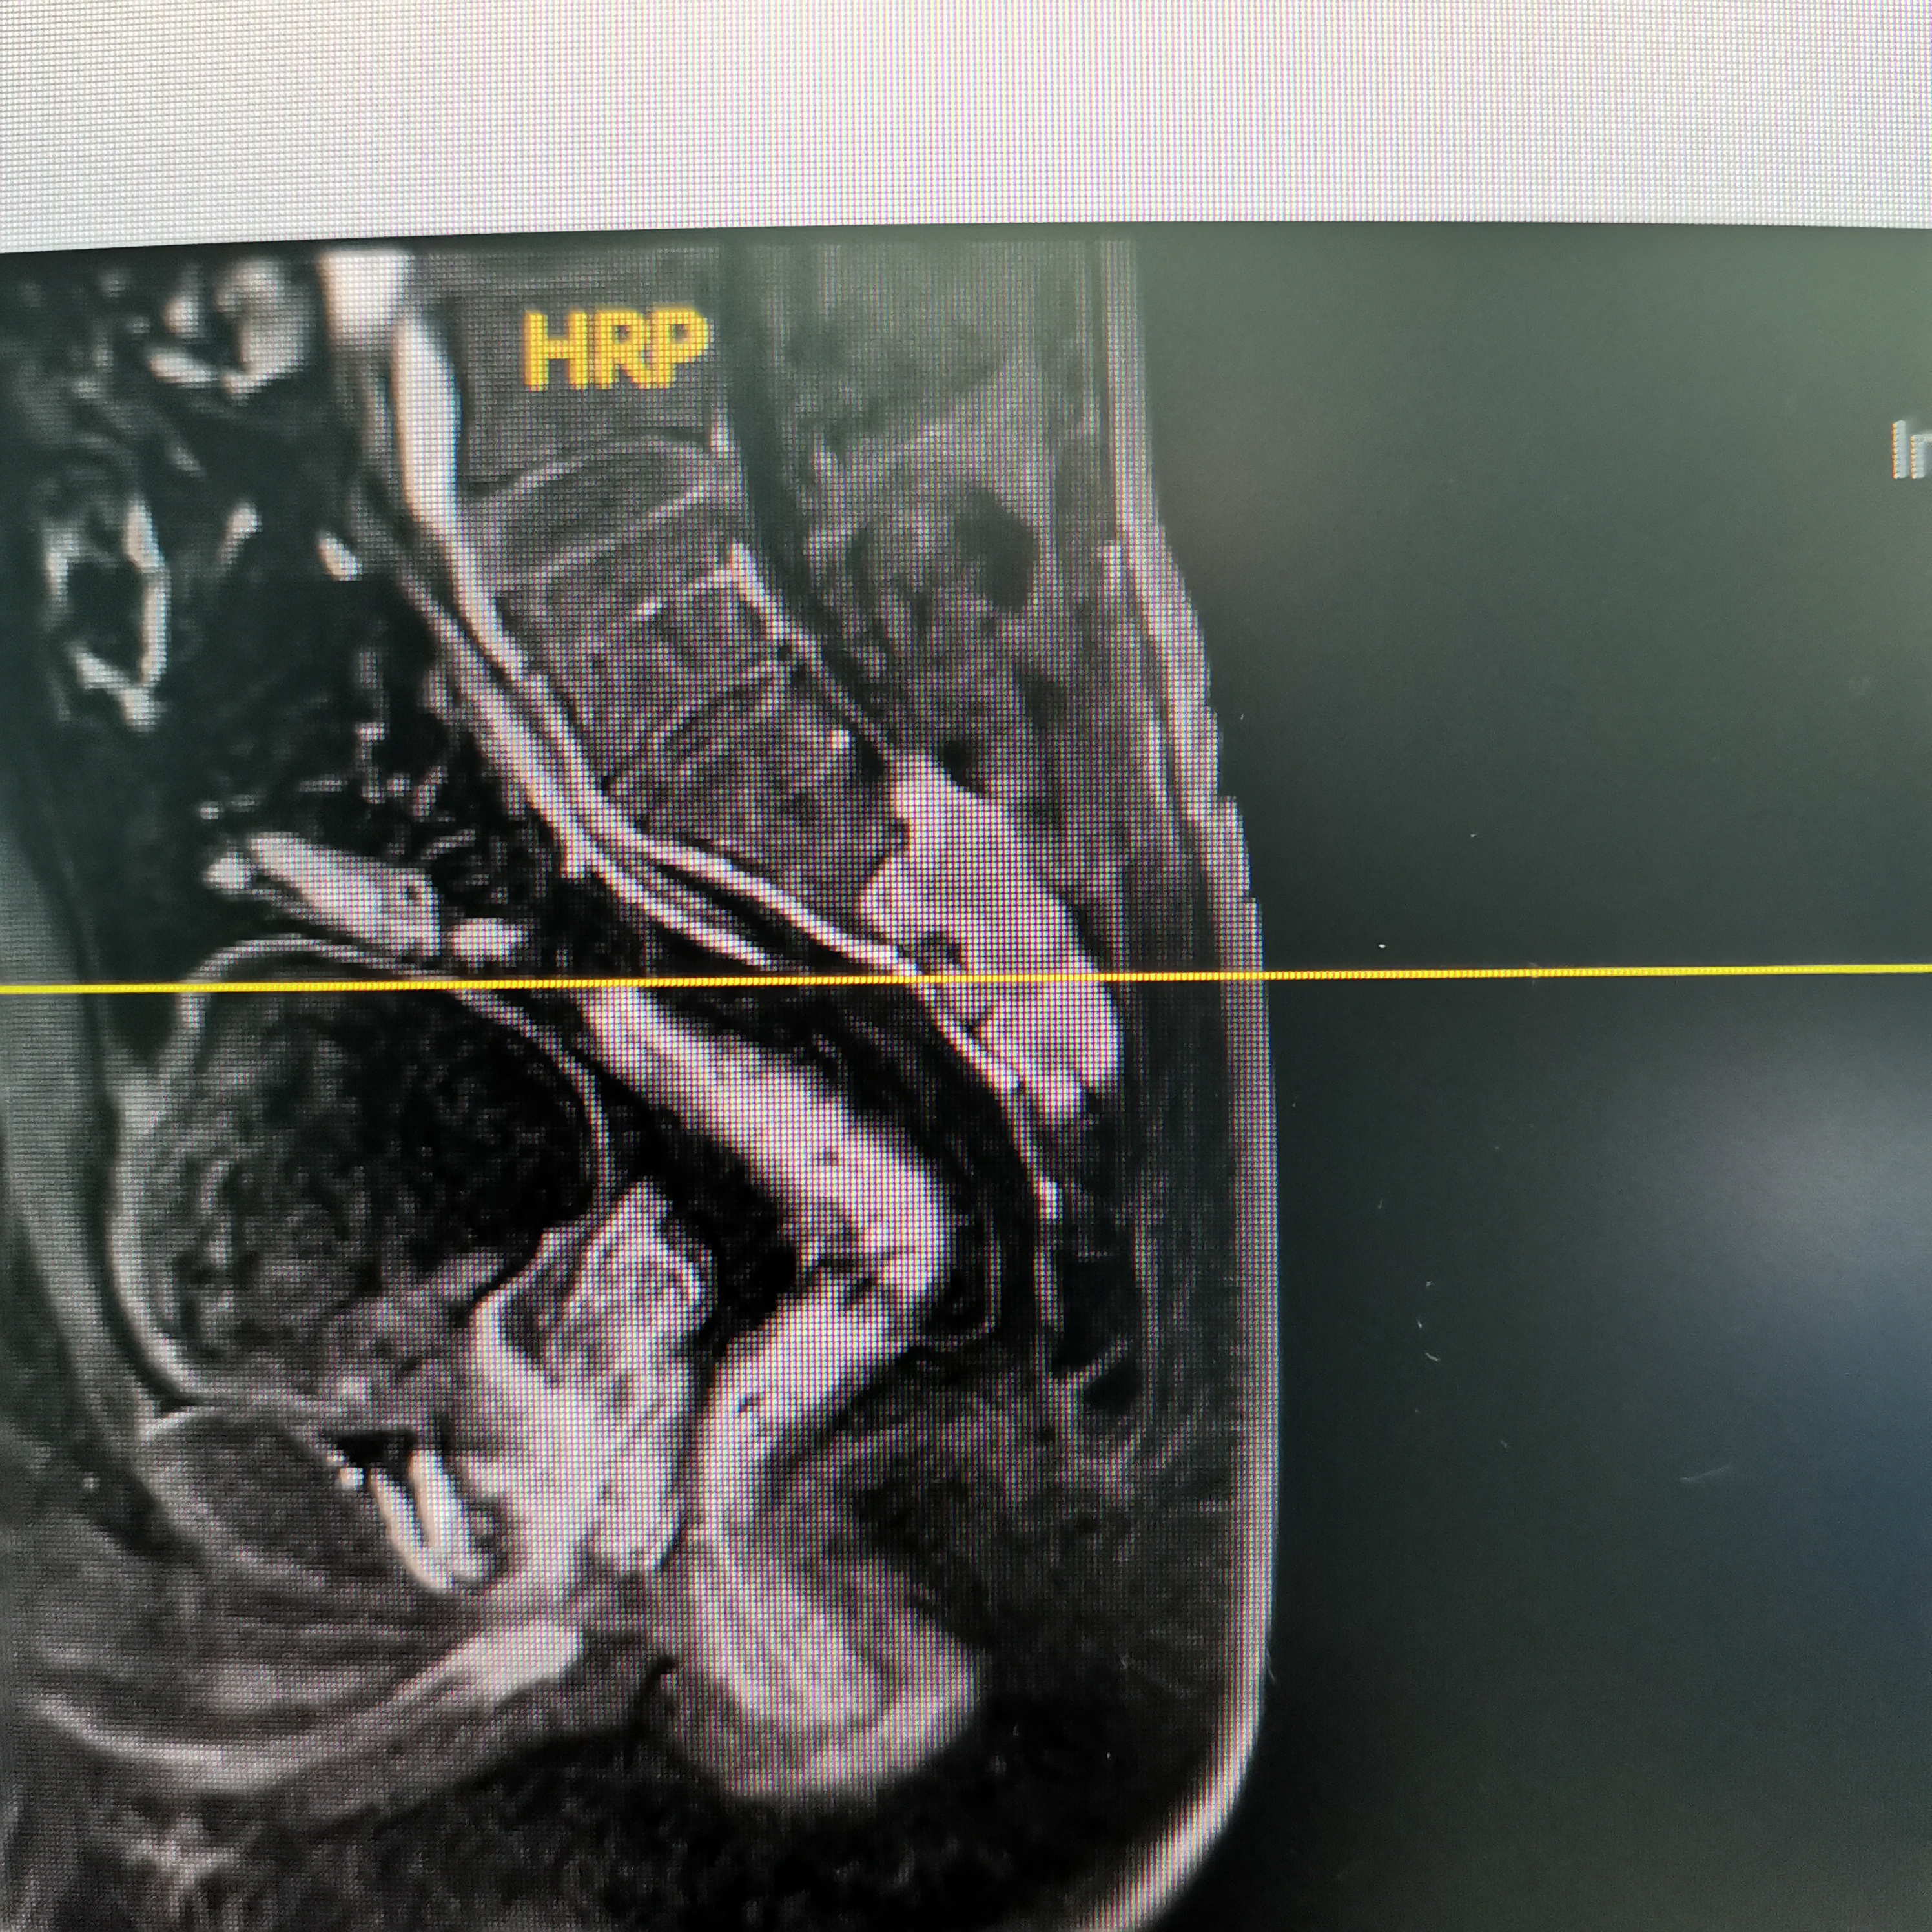

骶椎神经鞘瘤